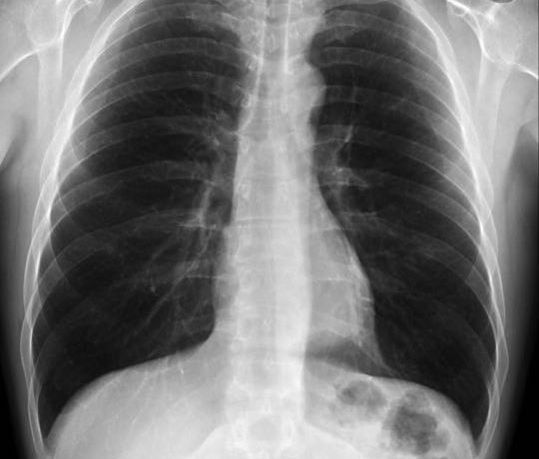

Më poshtë keni rentgenin e publikuar nga doktori Bytyqi si dhe një rentgen që tregon se si duhet të jenë në gjendje normale mushkëritë.